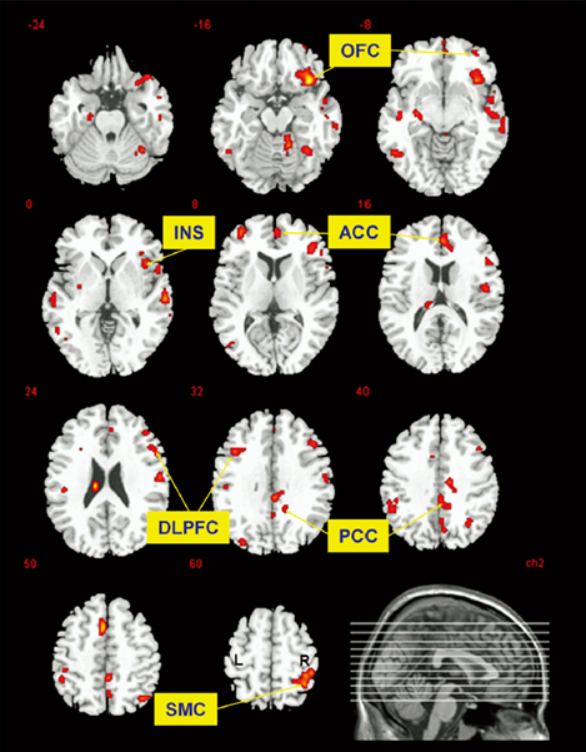

有人曾做过研究,让运动员跑30分钟,然后扫描其大脑。结果发现,他们大脑中阿片类物质和受体结合得更活跃了!

阿片受体就在大脑的神经系统中,如果激活了它,就会让你产生一种强烈的快感。像为爱鼓掌时,那种快乐的感jio也跟阿片系统密不可分。